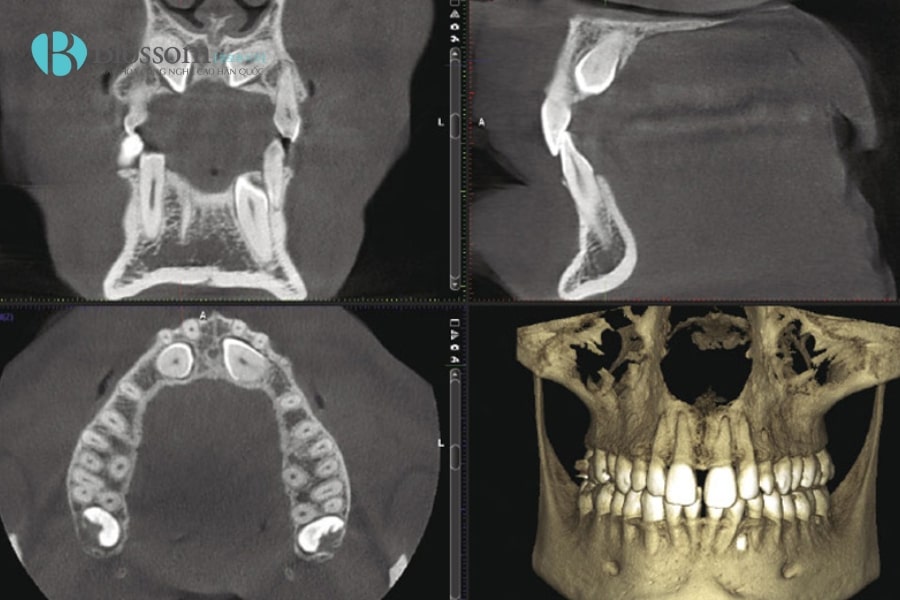

CT Cone Beam, viết tắt là CBCT (Cone Beam Computed Tomography), là kỹ thuật chụp hình ảnh 3D tiên tiến trong nha khoa. Máy sử dụng tia X hình nón quay 360 độ quanh đầu bệnh nhân để thu thập nhiều hình ảnh từ các góc khác nhau, sau đó tái tạo thành hình ảnh 3 chiều chi tiết của răng, xương hàm, mô mềm và ống thần kinh.

Khác với X-quang 2D truyền thống, CBCT cho phép quan sát toàn bộ cấu trúc hàm răng dưới nhiều góc độ, giúp bác sĩ đánh giá mật độ xương, vị trí dây thần kinh, xác định hướng đặt trụ Implant và lập kế hoạch điều trị chính xác. Quá trình chụp nhanh, không xâm lấn và ít tia bức xạ, mang lại sự an toàn và thoải mái cho bệnh nhân.

CT Cone Beam giúp đánh giá chính xác chất lượng và khối lượng xương hàm, vị trí dây thần kinh và mạch máu, từ đó lập kế hoạch cấy ghép Implant an toàn. Hình ảnh 3D cho phép chọn đường kính Implant phù hợp, dự đoán có cần ghép xương và tránh chèn ép các cấu trúc quan trọng như xoang hàm trên hay dây thần kinh hàm dưới, đảm bảo tuổi thọ lâu dài của trụ Implant.